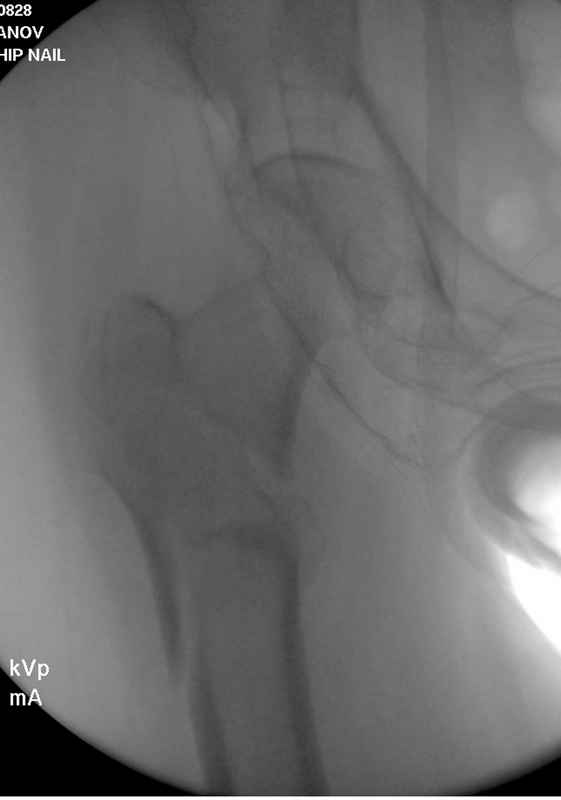

Здесь пара случаев фиксации похожих переломов:

первый высокоэнергетическая травма 36 лет

Здесь 83 года, травма в результате падения

судя по картинкам с ЭОПа явно использовались приемы непрямой репозиции под его контролем, а так же интраоперационный ЭОП-контроль положения винтов, без такого контроля операция может ухудшить ситуацию (опять же учтите сроки) т.к. результат буде зависеть в большей степени от искусства хирурга, а не от технологии